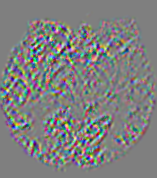

4.3.1 Advection Imaging via Advection-Diffusion

Slice #1Slice #2Slice #3Slice #4Slice #5Slice #6𝐕gt𝟐subscriptnormsuperscript𝐕gt2\|\bf{V}^{\text{gt}}\|_{2}Refer to captionRefer to captionRefer to captionRefer to captionRefer to captionRefer to caption𝐕est𝟐subscriptnormsuperscript𝐕est2\|\bf{V}^{\text{est}}\|_{2}Refer to captionRefer to captionRefer to captionRefer to captionRefer to captionRefer to captionRefer to caption1.51.51.51.21.21.20.90.90.90.60.60.60.30.30.30.00.00.0(mm/s)𝑚𝑚𝑠(mm/s)Destsuperscript𝐷estD^{\text{est}}Refer to captionRefer to captionRefer to captionRefer to captionRefer to captionRefer to captionRefer to caption0.0150.0150.0150.0120.0120.0120.0090.0090.0090.0060.0060.0060.0030.0030.0030.0000.0000.000(mm2/s)𝑚superscript𝑚2𝑠(mm^{2}/s)

Figure 14: PIANO identifiability testing: advection imaging via advection-diffusion. Top row shows 𝐕gt2subscriptnormsuperscript𝐕gt2\|{\bf{V}}^{\text{gt}}\|_{2} used for simulating ground truth pure advection. Rows below show the estimated 𝐕est2subscriptnormsuperscript𝐕est2\|{\bf{V}}^{\text{est}}\|_{2} and Destsuperscript𝐷estD^{\text{est}} on corresponding slices. Note that the plotted value scale for Destsuperscript𝐷estD^{\text{est}} is 0.01 of that for 𝐕gt2subscriptnormsuperscript𝐕gt2\|{\bf{V}}^{\text{gt}}\|_{2} and 𝐕est2subscriptnormsuperscript𝐕est2\|{\bf{V}}^{\text{est}}\|_{2}.

We use the same ‘Advection Imaging’ simulation of Sec. 4.2.1 as the concentration dataset for PIANO. However, instead of modeling pure advection (Eq. 15), we let PIANO estimate both velocity 𝐕estsuperscript𝐕est{\bf{V}}^{\text{est}} and diffusivity Destsuperscript𝐷estD^{\text{est}} via the advection-diffusion PDE (Eq. 2) underlying the proposed PIANO model. Fig. 14 shows the estimated 𝐕est2,subscriptnormsuperscript𝐕est2\|{\bf{V}}^{\text{est}}\|_{2}, and Destsuperscript𝐷estD^{\text{est}} fields for one patient. Although PIANO has the freedom to estimate both a velocity and a diffusivity field from pure advection, PIANO differentiates well between advection and diffusion: the estimated 𝐕est2subscriptnormsuperscript𝐕est2\|{\bf{V}}^{\text{est}}\|_{2} successfully reproduces the ground truth 𝐕gt2subscriptnormsuperscript𝐕gt2\|{\bf{V}}^{\text{gt}}\|_{2} governing the simulated advection process, just as it already did in the ‘Advection Imaging via Advection’ test (Fig. 12). More importantly, the estimated diffusivity Destsuperscript𝐷estD^{\text{est}} is orders of magnitudes smaller than 𝐕est2subscriptnormsuperscript𝐕est2\|{\bf{V}}^{\text{est}}\|_{2}, indicating the estimated diffusion is negligible compared to the estimated advection, which is highly consistent with the underlying pure advection of the simulated data.